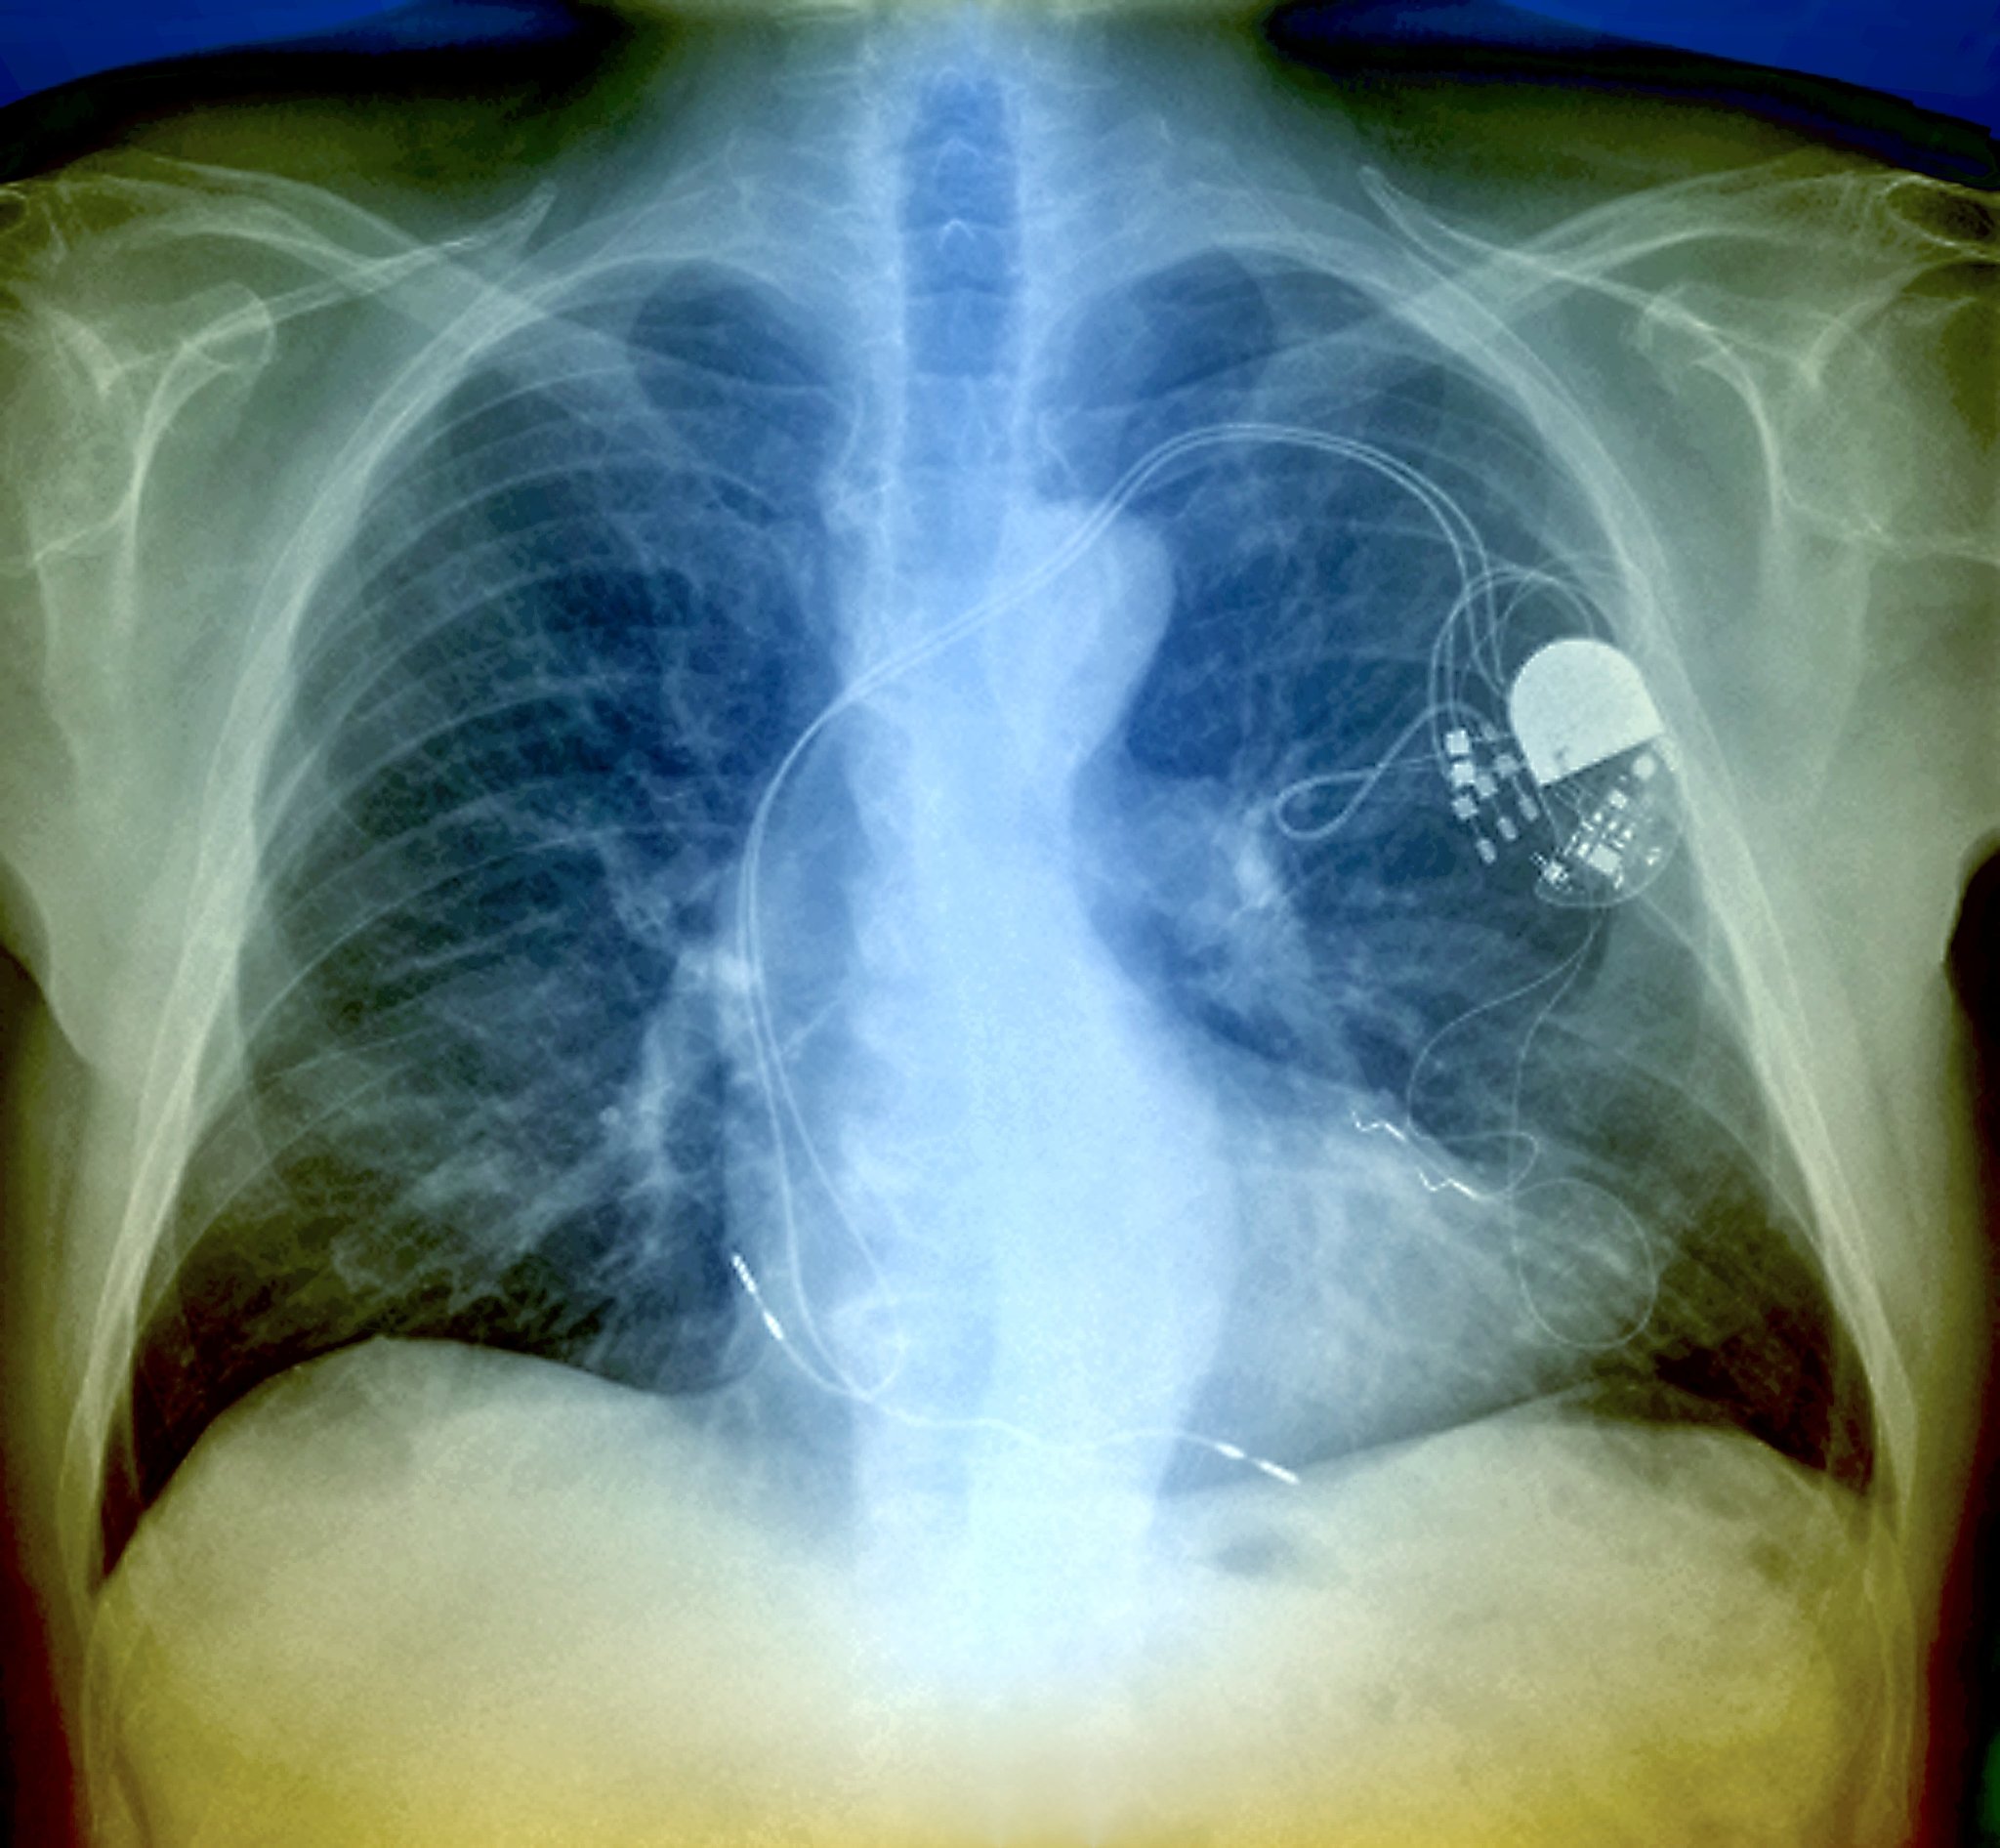

心脏起搏器一般用于以下情况:

1. 心室停顿或缓慢性心律失常:当心脏自己的起搏点出现问题时,会导致心跳不齐或停顿,这时需要安装心脏起搏器来维持心跳的正常节律。

2. 心力衰竭:心脏起搏器可以帮助心脏提高收缩力和输出量,减轻心力衰竭症状。

3. 心脏传导系统疾病:比如心房传导阻滞、房室传导阻滞等,这些疾病会导致心脏的电信号传导受阻,需要通过心脏起搏器来帮助心脏维持正常的节律。

4. 心脏手术后:有些心脏手术后需要安装心脏起搏器来辅助恢复心脏功能。

总之,安装心脏起搏器的具体情况需要根据患者的具体病情和临床表现而定,需要由医生进行综合评估和决策。

什么情况下需要安装心脏起搏器